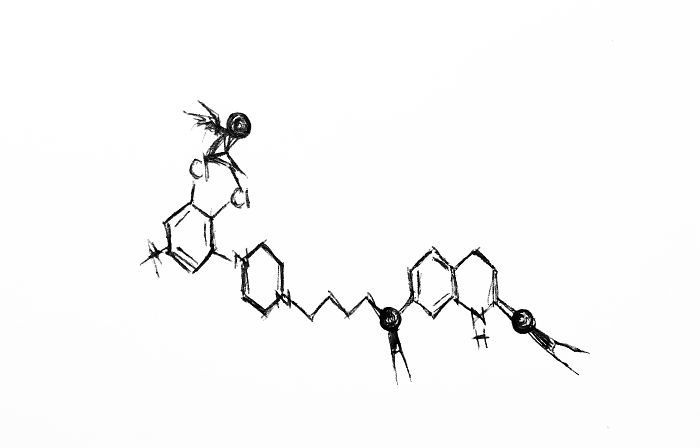

Aripiprazole

Flipping highs and slipping lows,

when will it end? No one knows.

Take the pill and hang on tight;

soon it will all be alright.